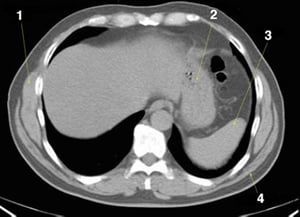

CT-Scan von Abdomen und Becken mit normaler Anatomie ohne Kontrastmittel (Folie 2)

1 = M. serratus anterior; 2 = Magen; 3 = Milz; 4 = M. latissimus dorsi.

© Springer Science+Business Media